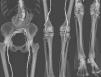

Objetivos. Evaluar la eficacia diagnóstica de la angiografía por tomografía computarizada multidetector (ATCM) en la arteriopatía de miembros inferiores (MMII), comparándola con angiografía por sustracción digital (ASD). Material y métodos. Se estudiaron 24 pacientes con arteriopatía de MMII. Se realizaron ATCM (4 detectores) y ADS realizando doble lectura entre las dos técnicas. Los territorios vasculares se dividieron para facilitar el análisis. Se calcularon sensibilidad (S), especificidad (E), prevalencia, valor predictivo positivo y negativo (VPP, VPN) y concordancia (test de Kappa). En arterias de tercera porción se estudió el rendimiento diagnóstico del ATCM realizando una curva ROC. Resultados. El estudio ATCM para la evaluación de la patología arterial mostró: una S menor en el estudio de la arteria ilíaca primitiva y arteria ilíaca interna (S: 0,65 y 0,71) con E de 0,94 y de 1; en los demás territorios vasculares obtuvimos S próximas a 1, disminuyendo algo la E. La concordancia fue muy alta (kappa entre 0,62 y 1) en todos los territorios estudiados. La ATCM mostró más longitud de vaso que la ASD. En la tercera porción el mejor rendimiento diagnóstico (ROC) se obtuvo en la lectura de vasos patológicos. Conclusión. La ATCM presentó alta fiabilidad en el estudio de la arteriopatía de MMII, con alta concordancia respecto a la ASD. En vasos tortuosos la ATCM visualiza mal las lesiones, en cambio en vasos rectos y en tercera porción el estudio con ATCM visualiza más segmentos vasculares.

Objectives. To evaluate the diagnostic efficacy of multidetector computed tomography angiography (MDCTA) in lower limb arteriopathy (LLA) by comparing it with digital subtraction angiography (DSA). Material and methods. Twenty-four patients with LLA were studied. All patients underwent MDCTA (four detectors) and DSA, with double reading between the two techniques. Vascular territories were divided to facilitate analysis. Sensitivity (S), specificity (Sp), prevalence, positive and negative predictive values (PPV, PNV), and concordance (Kappa test) were evaluated. In third-portion arteries, the diagnostic performance of MDCTA was evaluated using an ROC curve. Results. MDCTA study to evaluate arterial pathology showed: Lower sensitivity in the study of the internal iliac artery (S: 0.65 and 0.71) with Sp 0.94 and 1. In the other vascular territories, S approached 1, with a slight decrease in Sp. Concordance with DSA was very high (kappa between 0.62 and 1) in all of the territories studied. MDCTA showed greater vessel longitude than DSA. In the third portion, the best diagnostic performance (ROC) was obtained in the reading of pathological vessels. Conclusion. MDCTA was highly reliable in the study of LLA, with high concordance with DSA. In tortuous vessels, MDCTA depicted the lesions poorly; however, in straight vessels and third-portion vessels, MDCTA showed more vascular segments.